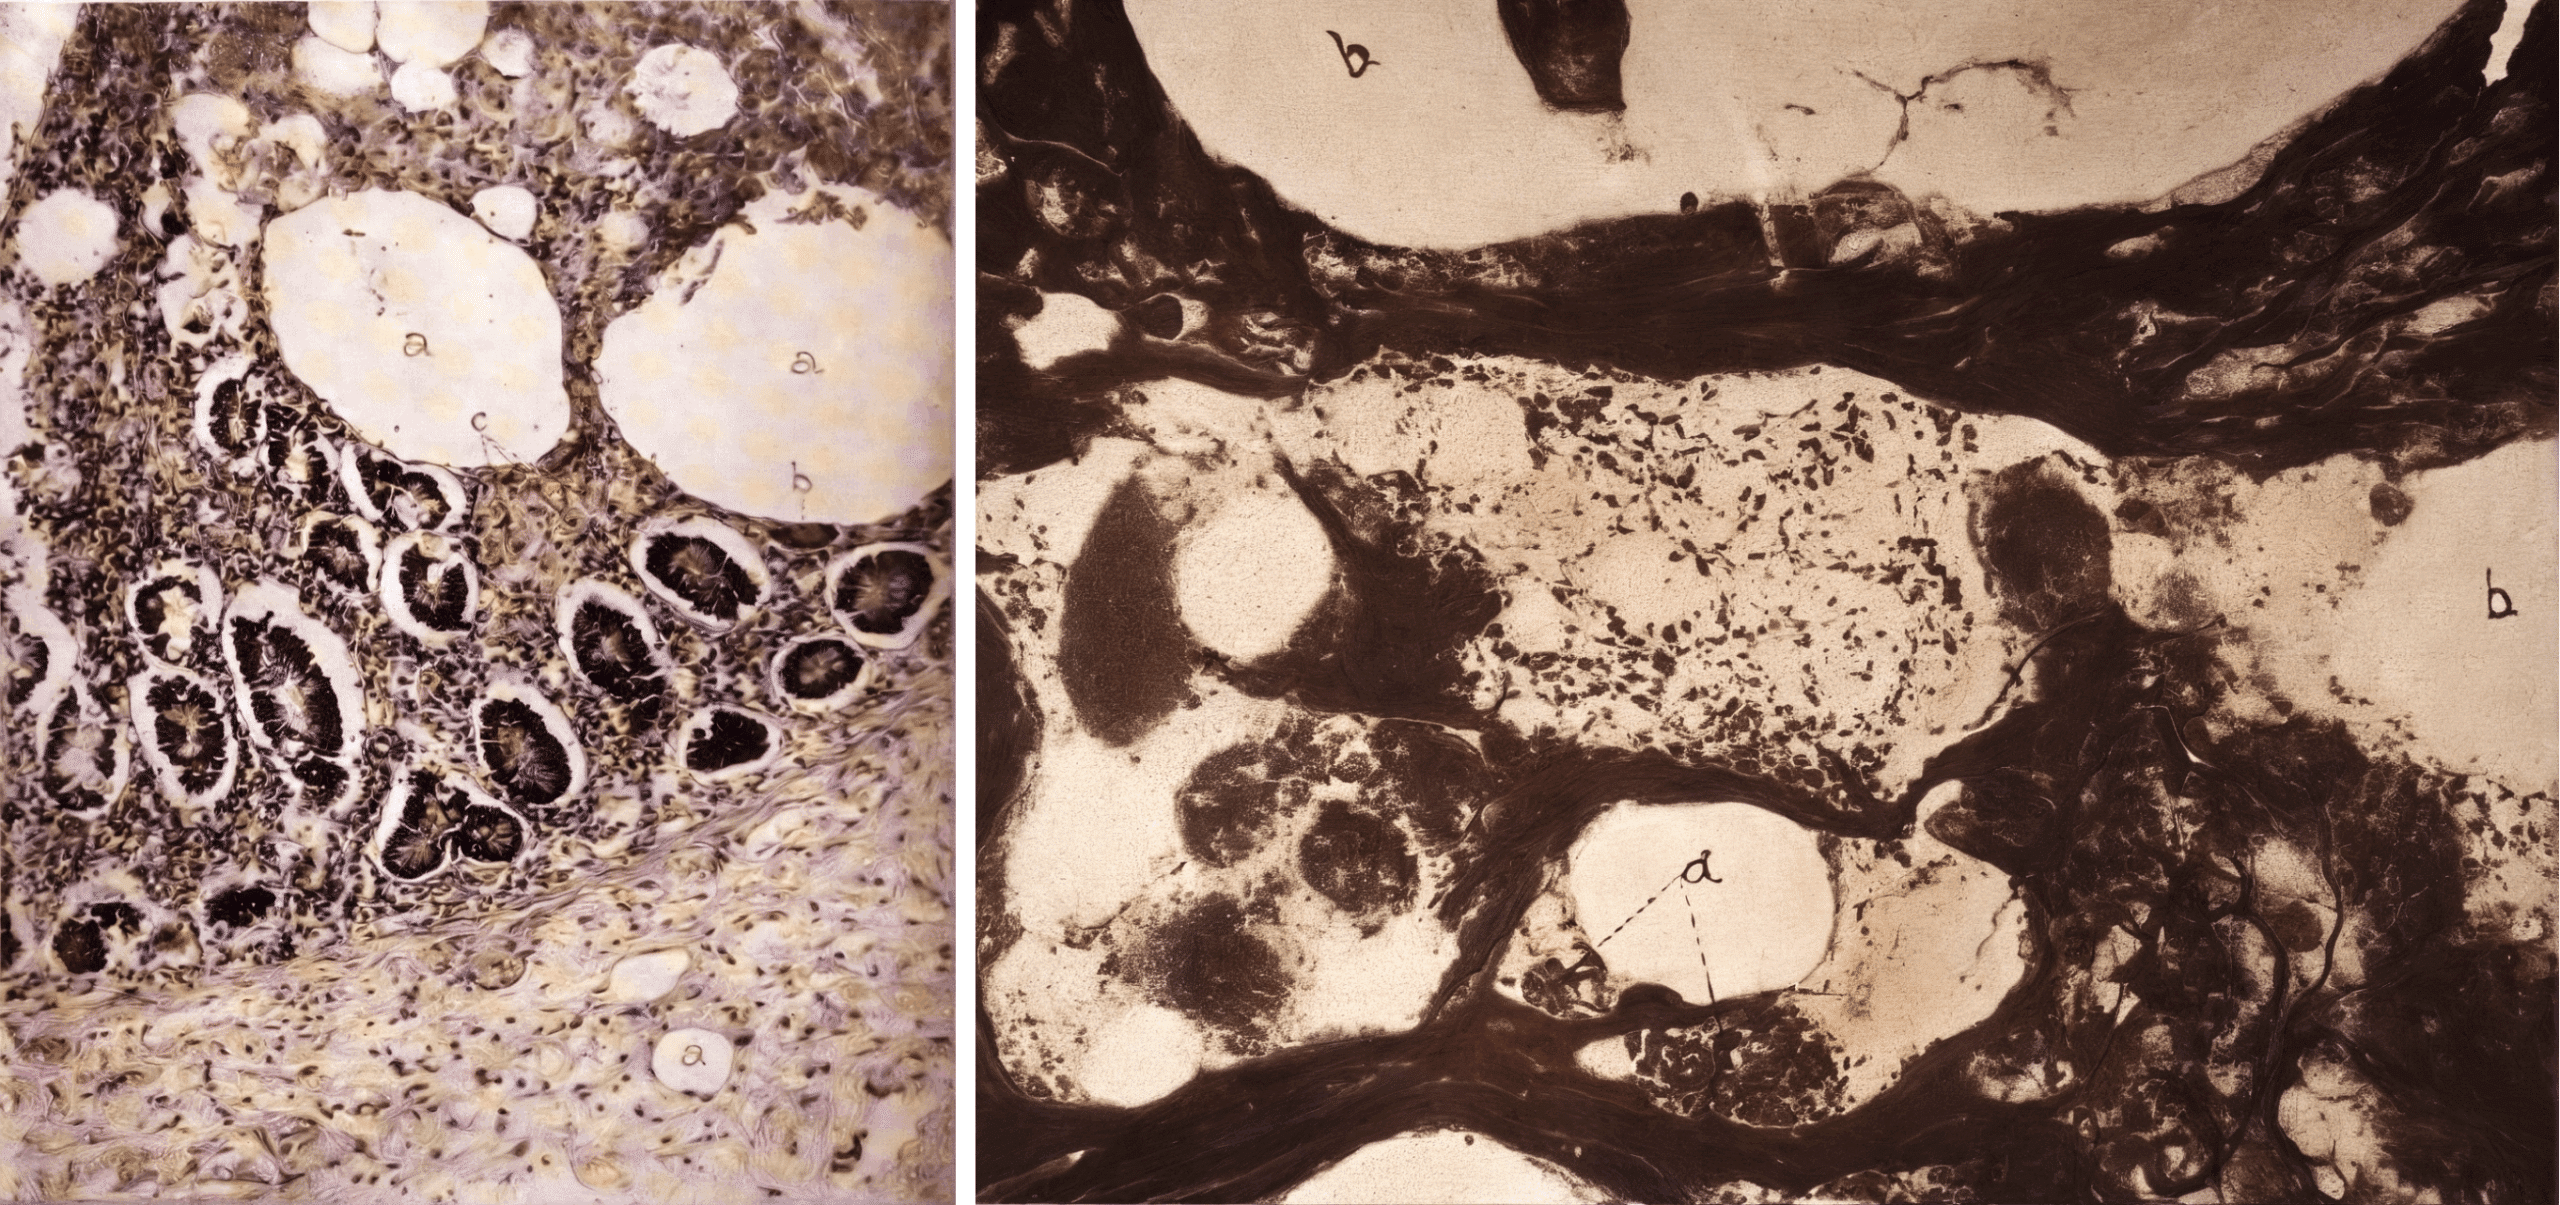

Right: Fig 9: Section of gland stained by Levaditi method. Vacuole (a) containing rod-shaped organism (?)

Whipple named the disorder “intestinal lipodystrophy” based on his belief that altered fat metabolism played a role in its pathogenesis. He also noted numerous rod-shaped organisms in a silver stained lymph node from his case, but the significance of this observation was not apparent in 1907.